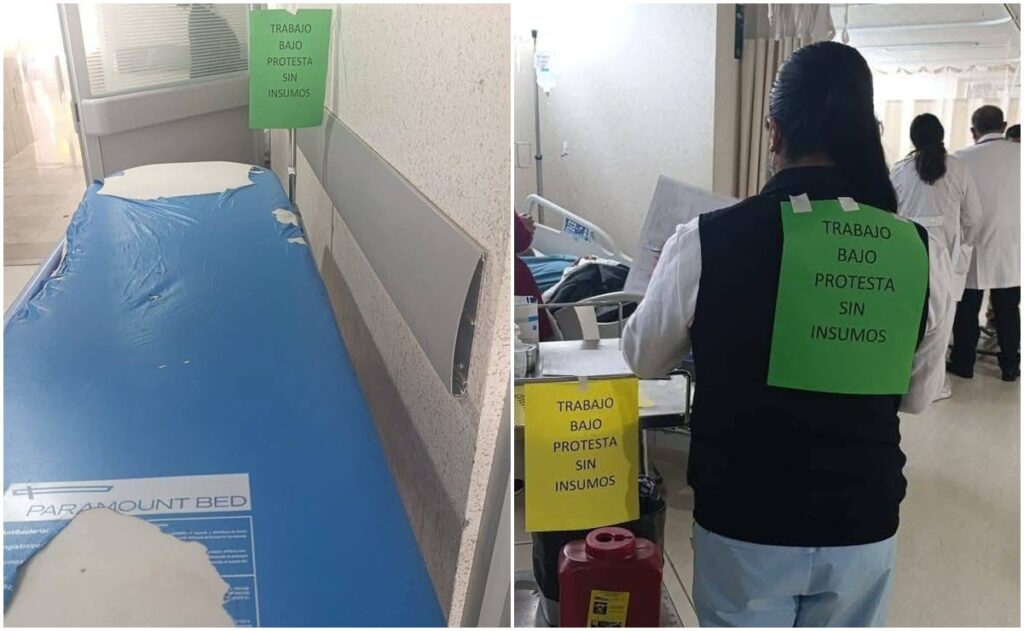

Trabajadores del ISSSTE en Oaxaca denuncian, ahora con mensajes en la espalda, falta de insumos y medicamentos

“Trabajo bajo protesta sin insumos” es la leyenda que el personal del hospital se colocó sobre su espalda para dar a conocer sus malas condiciones

Paran labores en Hospital Regional del ISSSTE en Oaxaca; denuncian falta de medicinas y pésimas condiciones

Acusan que es falsa la versión de la Dirección del ISSSTE en la que afirma que hay un abasto del 96 por ciento de los medicamentos

Colapsa el Hospital Regional del ISSSTE en Oaxaca; trabajadores denuncian riesgos sanitarios y estallan paro laboral

OAXACA, Oax., 28 de noviembre de 2025.— Trabajadores del Hospital Regional del ISSSTE en Oaxaca denunciaron este jueves un colapso operativo en la unidad médica y declararon un paro laboral parcial para exigir atención inmediata a una crisis que —aseguran— ha sido ignorada durante meses por autoridades federales y estatales. Según el personal inconforme, los […]